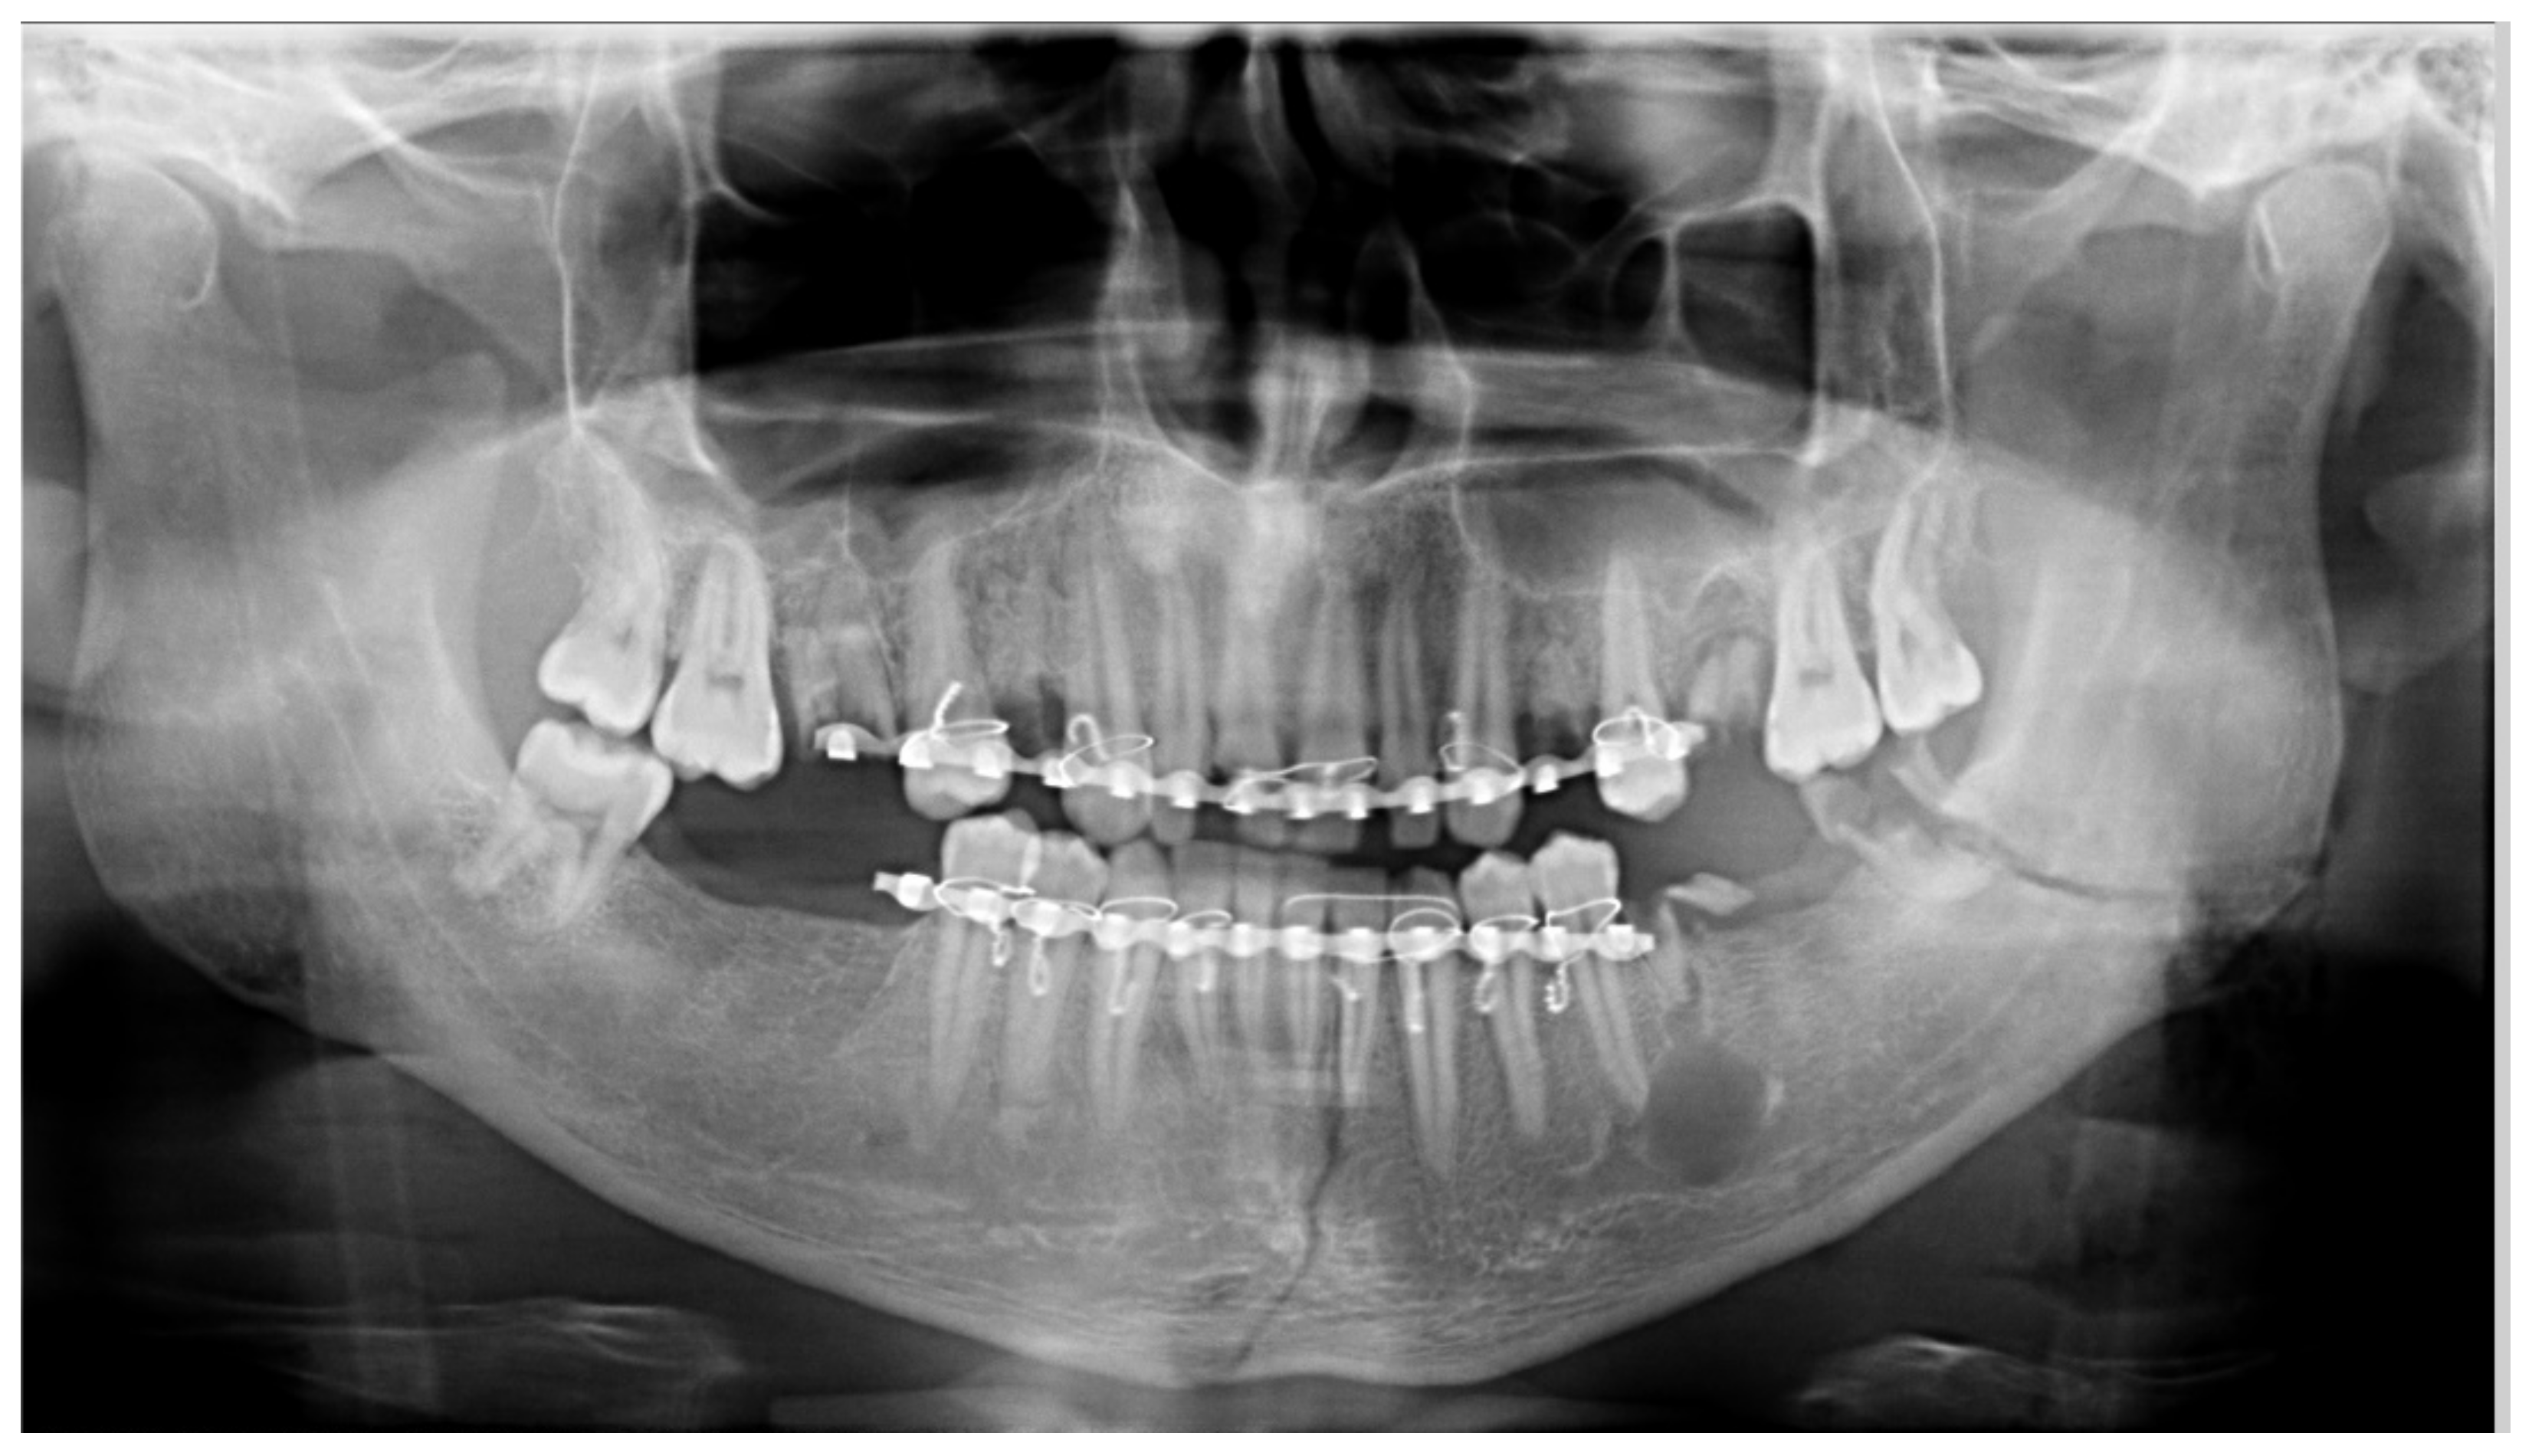

| Absence of bite-block | 28 | 93.33 | 51.85 | [78.68–98.15] |

| Radiographs with bimaxillary immobilization errors | 23 | 76.66 | 62.16 | [59.07–88.21] * |